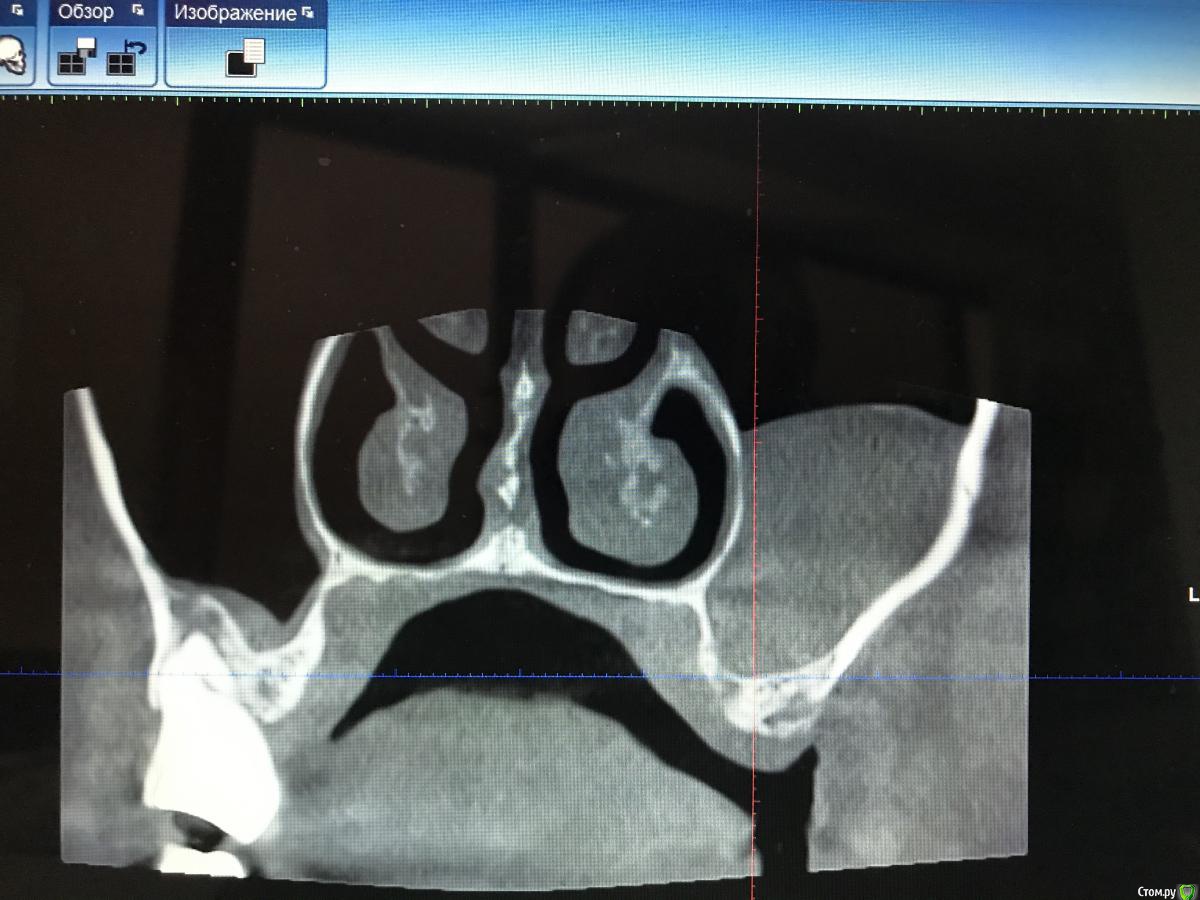

dr.Dre Опубликовано 4 августа, 2020 Поделиться Опубликовано 4 августа, 2020 Добрый день коллеги ,планируеться синус,ничего не беспокоит .Убирать самому или ,направить к лору как думаете ? Ссылка на комментарий

колесников Опубликовано 5 августа, 2020 Поделиться Опубликовано 5 августа, 2020 Вообще не трогайте. Вы что Д’Артаньян ? Очень толстая стенка синуса,сделайте закрытый синус. Киста или сама лопнет или пациент к Лору обратится если что то забеспокоит. Качество кости не смущает? Что за пациент? Как выглядит костная ткань на н/ч? Эмаль не изменена? Сопутствующие патологии имеются? Ссылка на комментарий

Snow Doc Опубликовано 1 сентября, 2020 Поделиться Опубликовано 1 сентября, 2020 Плюсую к 6мм Тл. Ещё и септа неприятная, по всей видимости, для открытого. Ссылка на комментарий